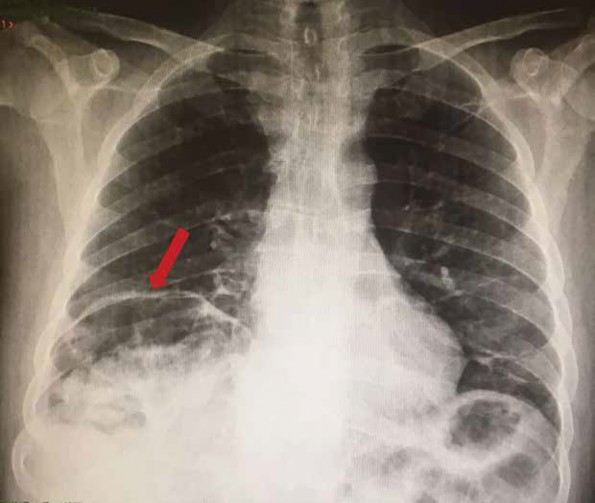

Se obtuvo radiografía anteroposterior de tórax, la cual reveló una imagen radiolúcida por debajo del diafragma del lado derecho (figura 1). Se solicitó tomografía contrastada de abdomen, en la cual se observó -en los cortes a nivel de hígado-interposición de imagen hipodensa con contenido heterogéneo que corresponde al colon e integridad del diafragma (figura 2).

Figura 1 (AP de tórax). La flecha señala la imagen radiolúcida por encima del hígado, que corresponde al colon derecho

Al analizar la radiografía de tórax inicial y observar la imagen radiolúcida por encima del hígado, es fácil suponer que ocurrió una ruptura del diafragma; sin embargo, al completar el estudio con una tomografía, se pudo descartar este diagnóstico y corroborar la presencia de síndrome de Chilaiditi con la interposición del colon y el hígado y el signo de Joubert positivo (perdida de la matidez hepática a la percusión).